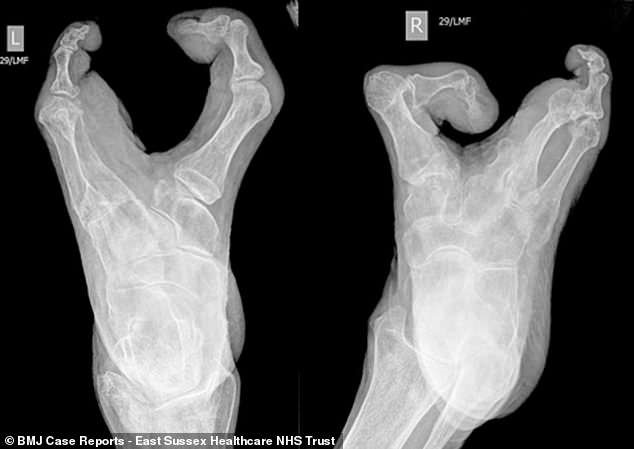

Bà không có ngón tay cái và mỗi bàn tay chỉ còn lại 3 ngón tay. Bà cũng không có ngón chân cái, các ngón chân còn lại dính lại với nhau, khiến bàn chân của bà trông như chiếc càng tôm hùm.

Cụ bà được chẩn đoán mắc dị tật phân chia bàn tay/bàn chân (SHFM). Đây là một tình trạng hiếm gặp, tỷ lệ mắc bệnh là 1/18.000 người. Khuyết tật này có thể do di truyền hoặc biến đổi gen từ lúc trong bụng mẹ.

Ảnh chụp X-quang cho thấy bàn chân bà giống hệt càng tôm hùm